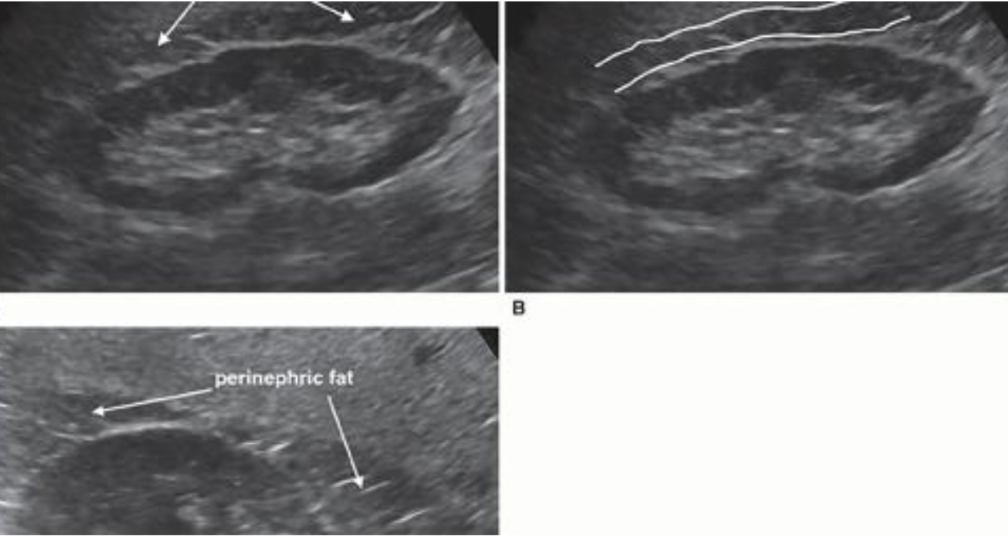

An image dividing the right kidney into anterior and posterior sections describes the:

coronal plane

The right kidney is in contact with the:

liver, colon, and adrenal gland

renal pyramids

renal artery

vascular supply

renal parenchyma